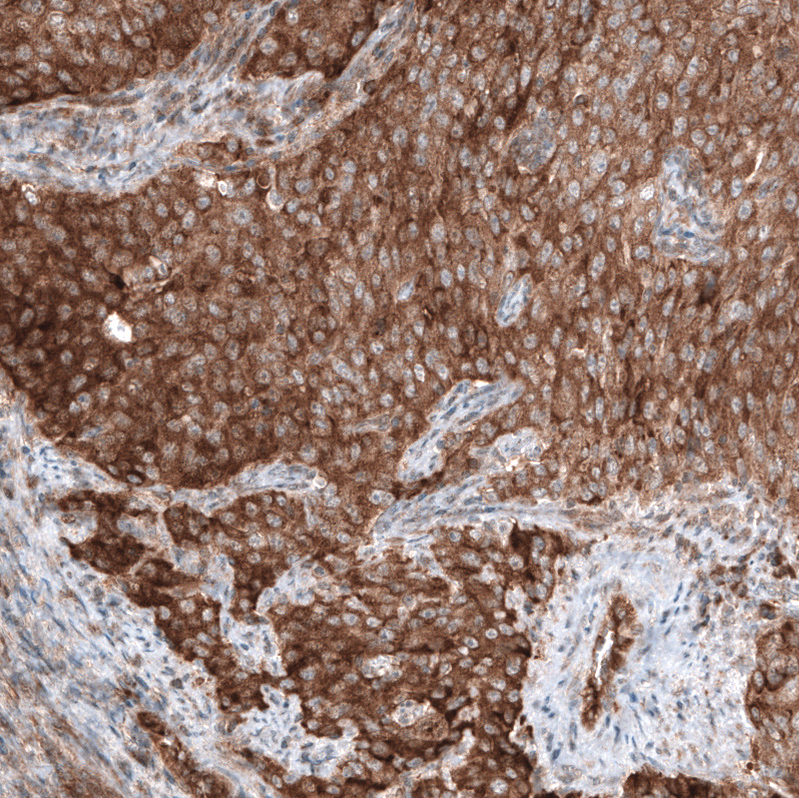

Immunohistochemical staining of human breast cancer shows strong cytoplasmic positivity in tumor cells.